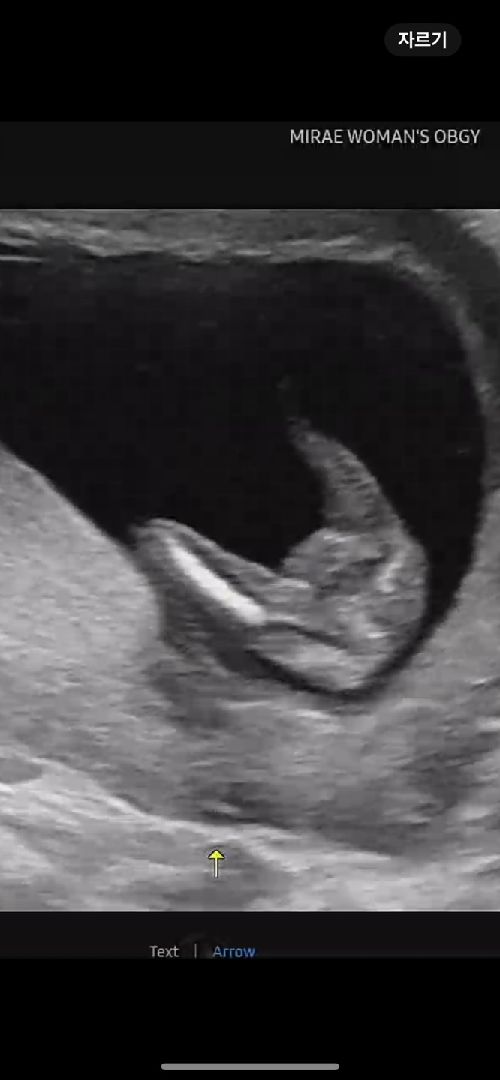

선배님들 성별 질문이요

성별이 무엇일지요..? 어두운부분때문에 부각되어 보이는건지요..

16주 미만이면 옆모습으로 봐야해요!